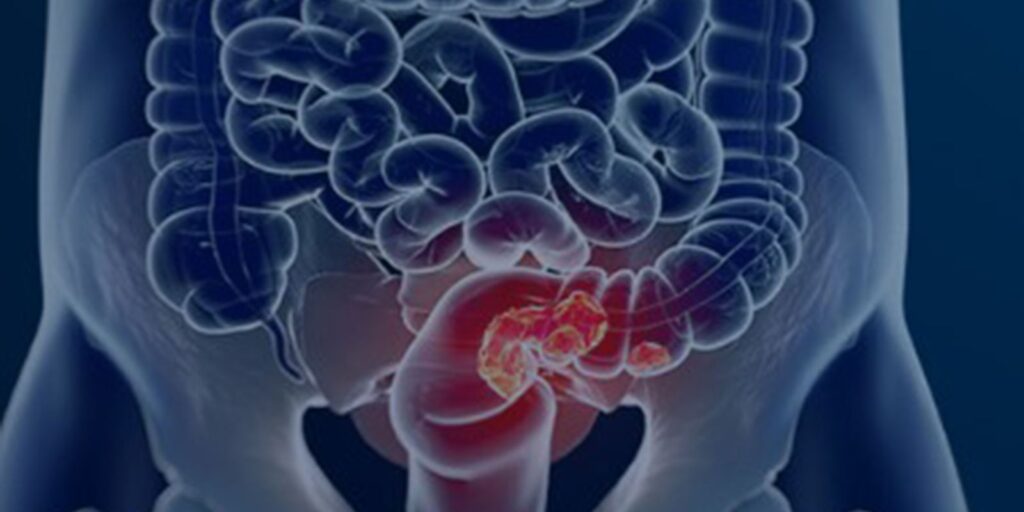

Lançado nesta quinta-feira (27), quando se comemora o Dia Nacional de Combate ao Câncer, o estudo Câncer colorretal no Brasil – O desafio invisível do diagnóstico, da Fundação do Câncer revela que, dos 177 mil casos da doença registrados em hospitais públicos e privados do país, no período de 2013 a 2022, mais de 60% foram diagnosticados em estágios avançados da doença.

Os dados mostram que o avanço da doença e a demora no diagnóstico, reduz de forma acentuada a possibilidade de cura.

Em entrevista à Agência Brasil, o diretor-executivo da Fundação do Câncer, cirurgião oncológico Luiz Augusto Maltoni, chama a atenção o volume de casos de câncer colorretal (CCR) que chegam no sistema em estágio avançado”, confirmou em entrevista à Agência Brasil o diretor-executivo da Fundação do Câncer, cirurgião oncológico Luiz Augusto Maltoni.

“Se analisarmos o país como um todo, os dados mostram que 50% das pessoas chegam no estágio já metastático, estágio 4, e mais 25% no estágio 3. Somando os estágios, são mais de 70%, o que é uma catástrofe.”